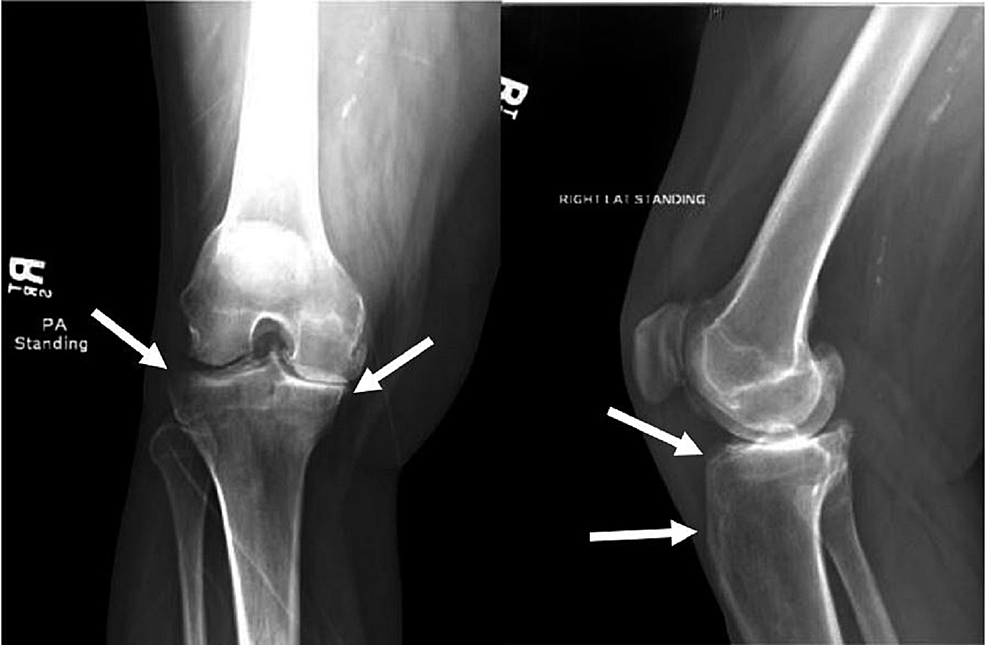

From www.semanticscholar.org

Figure 1 from Salmonella osteomyelitis in a patient with adultonset Salmonella Osteomyelitis Symptoms Salmonella species are a common cause of osteomyelitis in developing countries and among patients with sickle cell disease. It is an acute or chronic inflammatory process involving the bone and its structures secondary to infection with. Salmonella osteomyelitis is often overlooked, causing misdiagnoses and delays. Bone infection is called osteomyelitis. Fever and back or neck pain remain the main symptoms. Salmonella Osteomyelitis Symptoms.